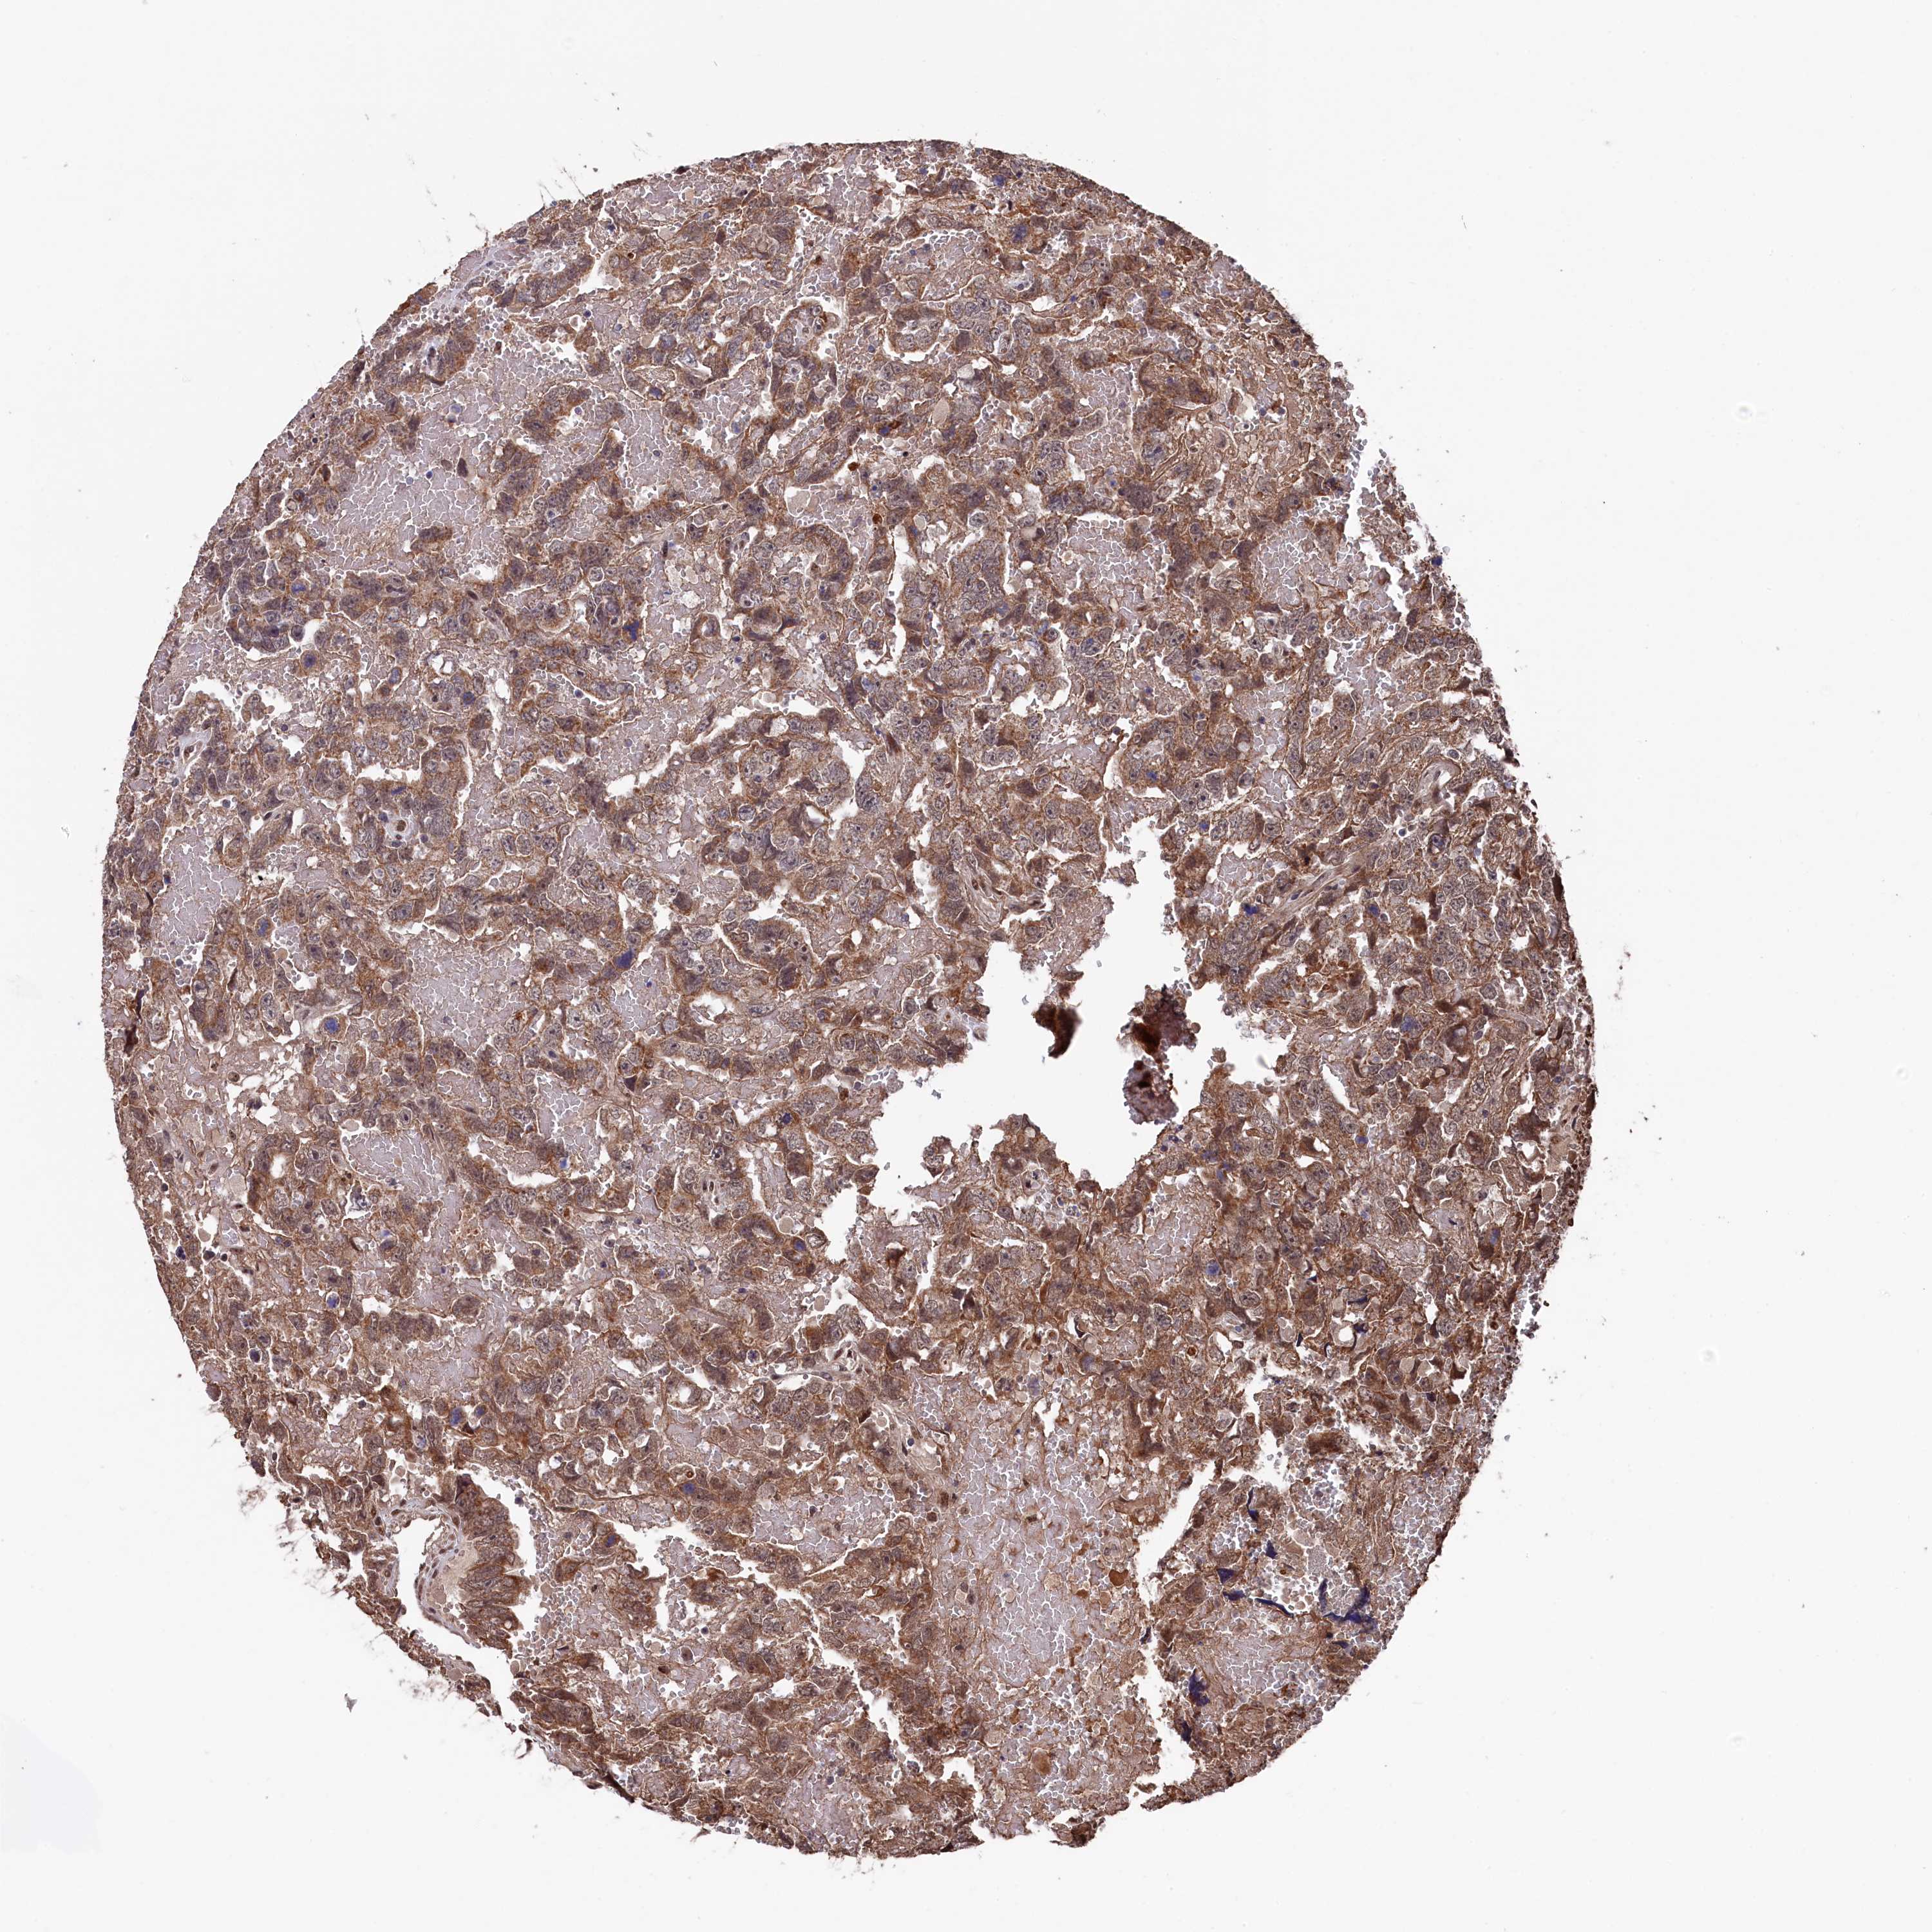

TESTIS CANCER - Protein expressioni

A mouse-over function shows sample information and annotation data. Click on an image to view it in a full screen mode. Samples can be filtered based on level of antibody staining by selecting one or several of the following categories: high, medium, low and not detected. The assay and annotation is described here.

Note that samples used for immunohistochemistry by the Human Protein Atlas do not correspond to samples in the TCGA dataset.

Antibody stainingi

Antibody staining in the annotated cell types in the current human tissue is reported as not detected, low, medium, or high, based on conventional immunohistochemistry profiling in selected tissues. This score is based on the combination of the staining intensity and fraction of stained cells.

Each image is clickable and will lead to virtual microscopy that enables deeper exploration of all samples and also displays staining intensity scores, fraction scores and subcellular localization as well as patient and tissue information for each sample.

Antibody HPA040262

Staining

High

Medium

Low

Not detected

Intensity

Strong

Moderate

Weak

Negative

Quantity

>75%

75%-25%

<25%

None

Location

Nuclear

Cytoplasmic/membranous

Cytoplasmic/membranous,nuclear

Carcinoma, Embryonal, NOS

Seminoma, NOS

Urothelial carcinoma, High grade